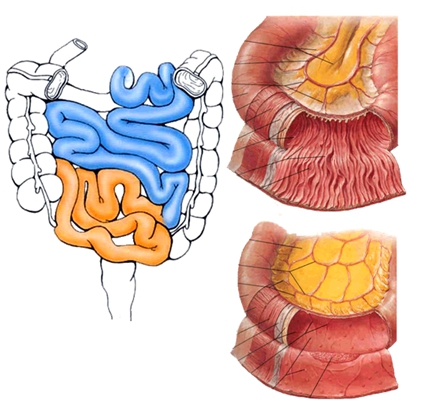

盲腸的位置 (50)

盲腸的位置 (6)

盲腸的位置 (7)

盲腸的位置 (8)

盲腸的位置 (9)

盲腸的位置 (46)

盲腸的位置 (47)

盲腸的位置 (48)

盲腸的位置 (49)

盲腸的位置 (5)

盲腸的位置 (42)

盲腸的位置 (43)

盲腸的位置 (44)

盲腸的位置 (45)

盲腸的位置 (41)

盲腸的位置 (40)

盲腸的位置 (30)

盲腸的位置 (31)

盲腸的位置 (32)

盲腸的位置 (33)